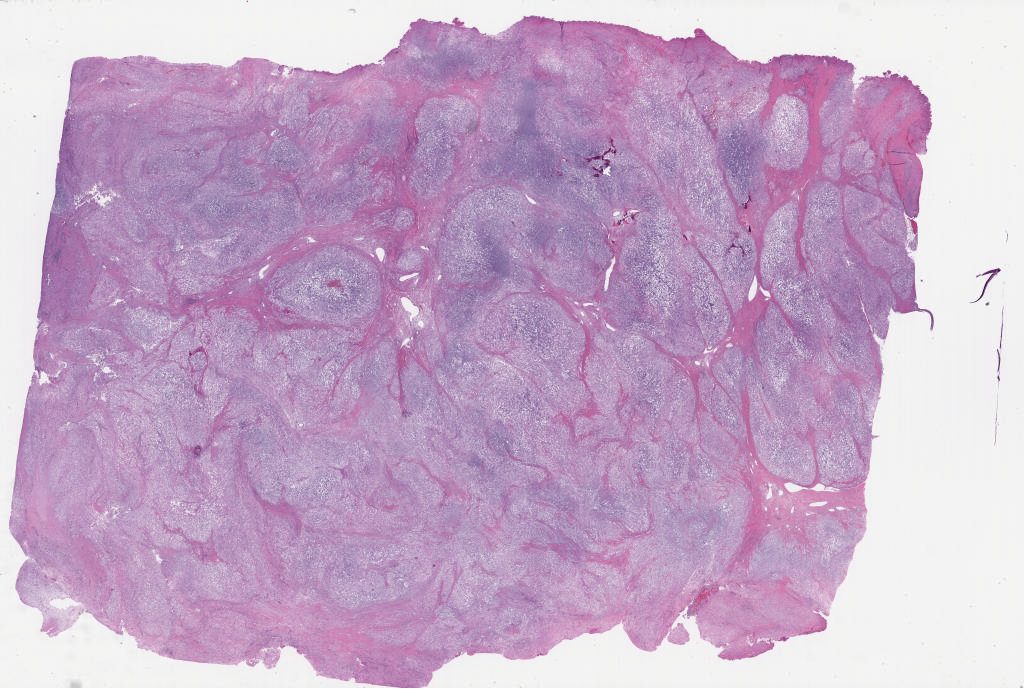

Case4.svs

103584

x

80916

@

40X